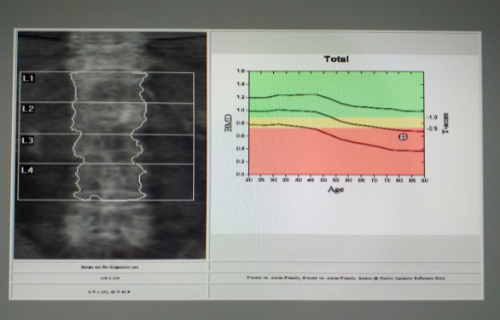

A bone scan is categorized as a nuclear medicine method because it involves a small amount of radiation entering the body. A radioactive tracer is first injected into the person. A few hours later the person will then have their body scanned with a device designed to detect the radioactive material. The tracer can show abnormalities on the scan that could indicate a bone problem. A score below -1 but not at -2.5 means osteopenia. Osteoporosis is when the score is -2.5 and worse.

A bone density scan is also called a dual energy X-ray absorptiometry (DEXA) and is a test done to look at the density of the bone tissue.

A bone density scan is done to look at how dense your bone tissue is. The scan is done to evaluate a person’s risk of getting osteoporosis. Osteoporosis is porous bones, which makes a person likely to break a bone.

The DEXA is similar to an X-ray and you lie on a table. The machine, though, uses two different types of X-ray beams. It produces both a high-energy and a low-energy X-ray beam. The idea is to measure how well the rays pass through the bone so as to estimate the density of the tissue.

- A bone density scan is used to look at the level of mineral density in bones and to assess a person’s risk of osteopenia and osteoporosis.

Bone density scans have a high accuracy allowing doctors to determine what amount of bone loss has occurred and if the person has osteopenia or osteoporosis.